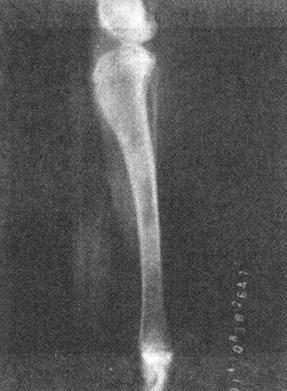

4)全骨炎 又称嗜酸性全骨炎,是一种长骨疼痛性炎症。多见于5~18月龄大型犬,尤以德国牧羊犬多发。X线表现为在骨干或干骺端的骨髓腔内出现斑块状致密阴影,骨小梁结构模糊不清(图1-4)。骨内膜增厚,骨膜新生骨反应。

图1-4 犬胫骨全骨炎

侧位显示胫骨上下1/3处骨髓腔内出现致密阴影